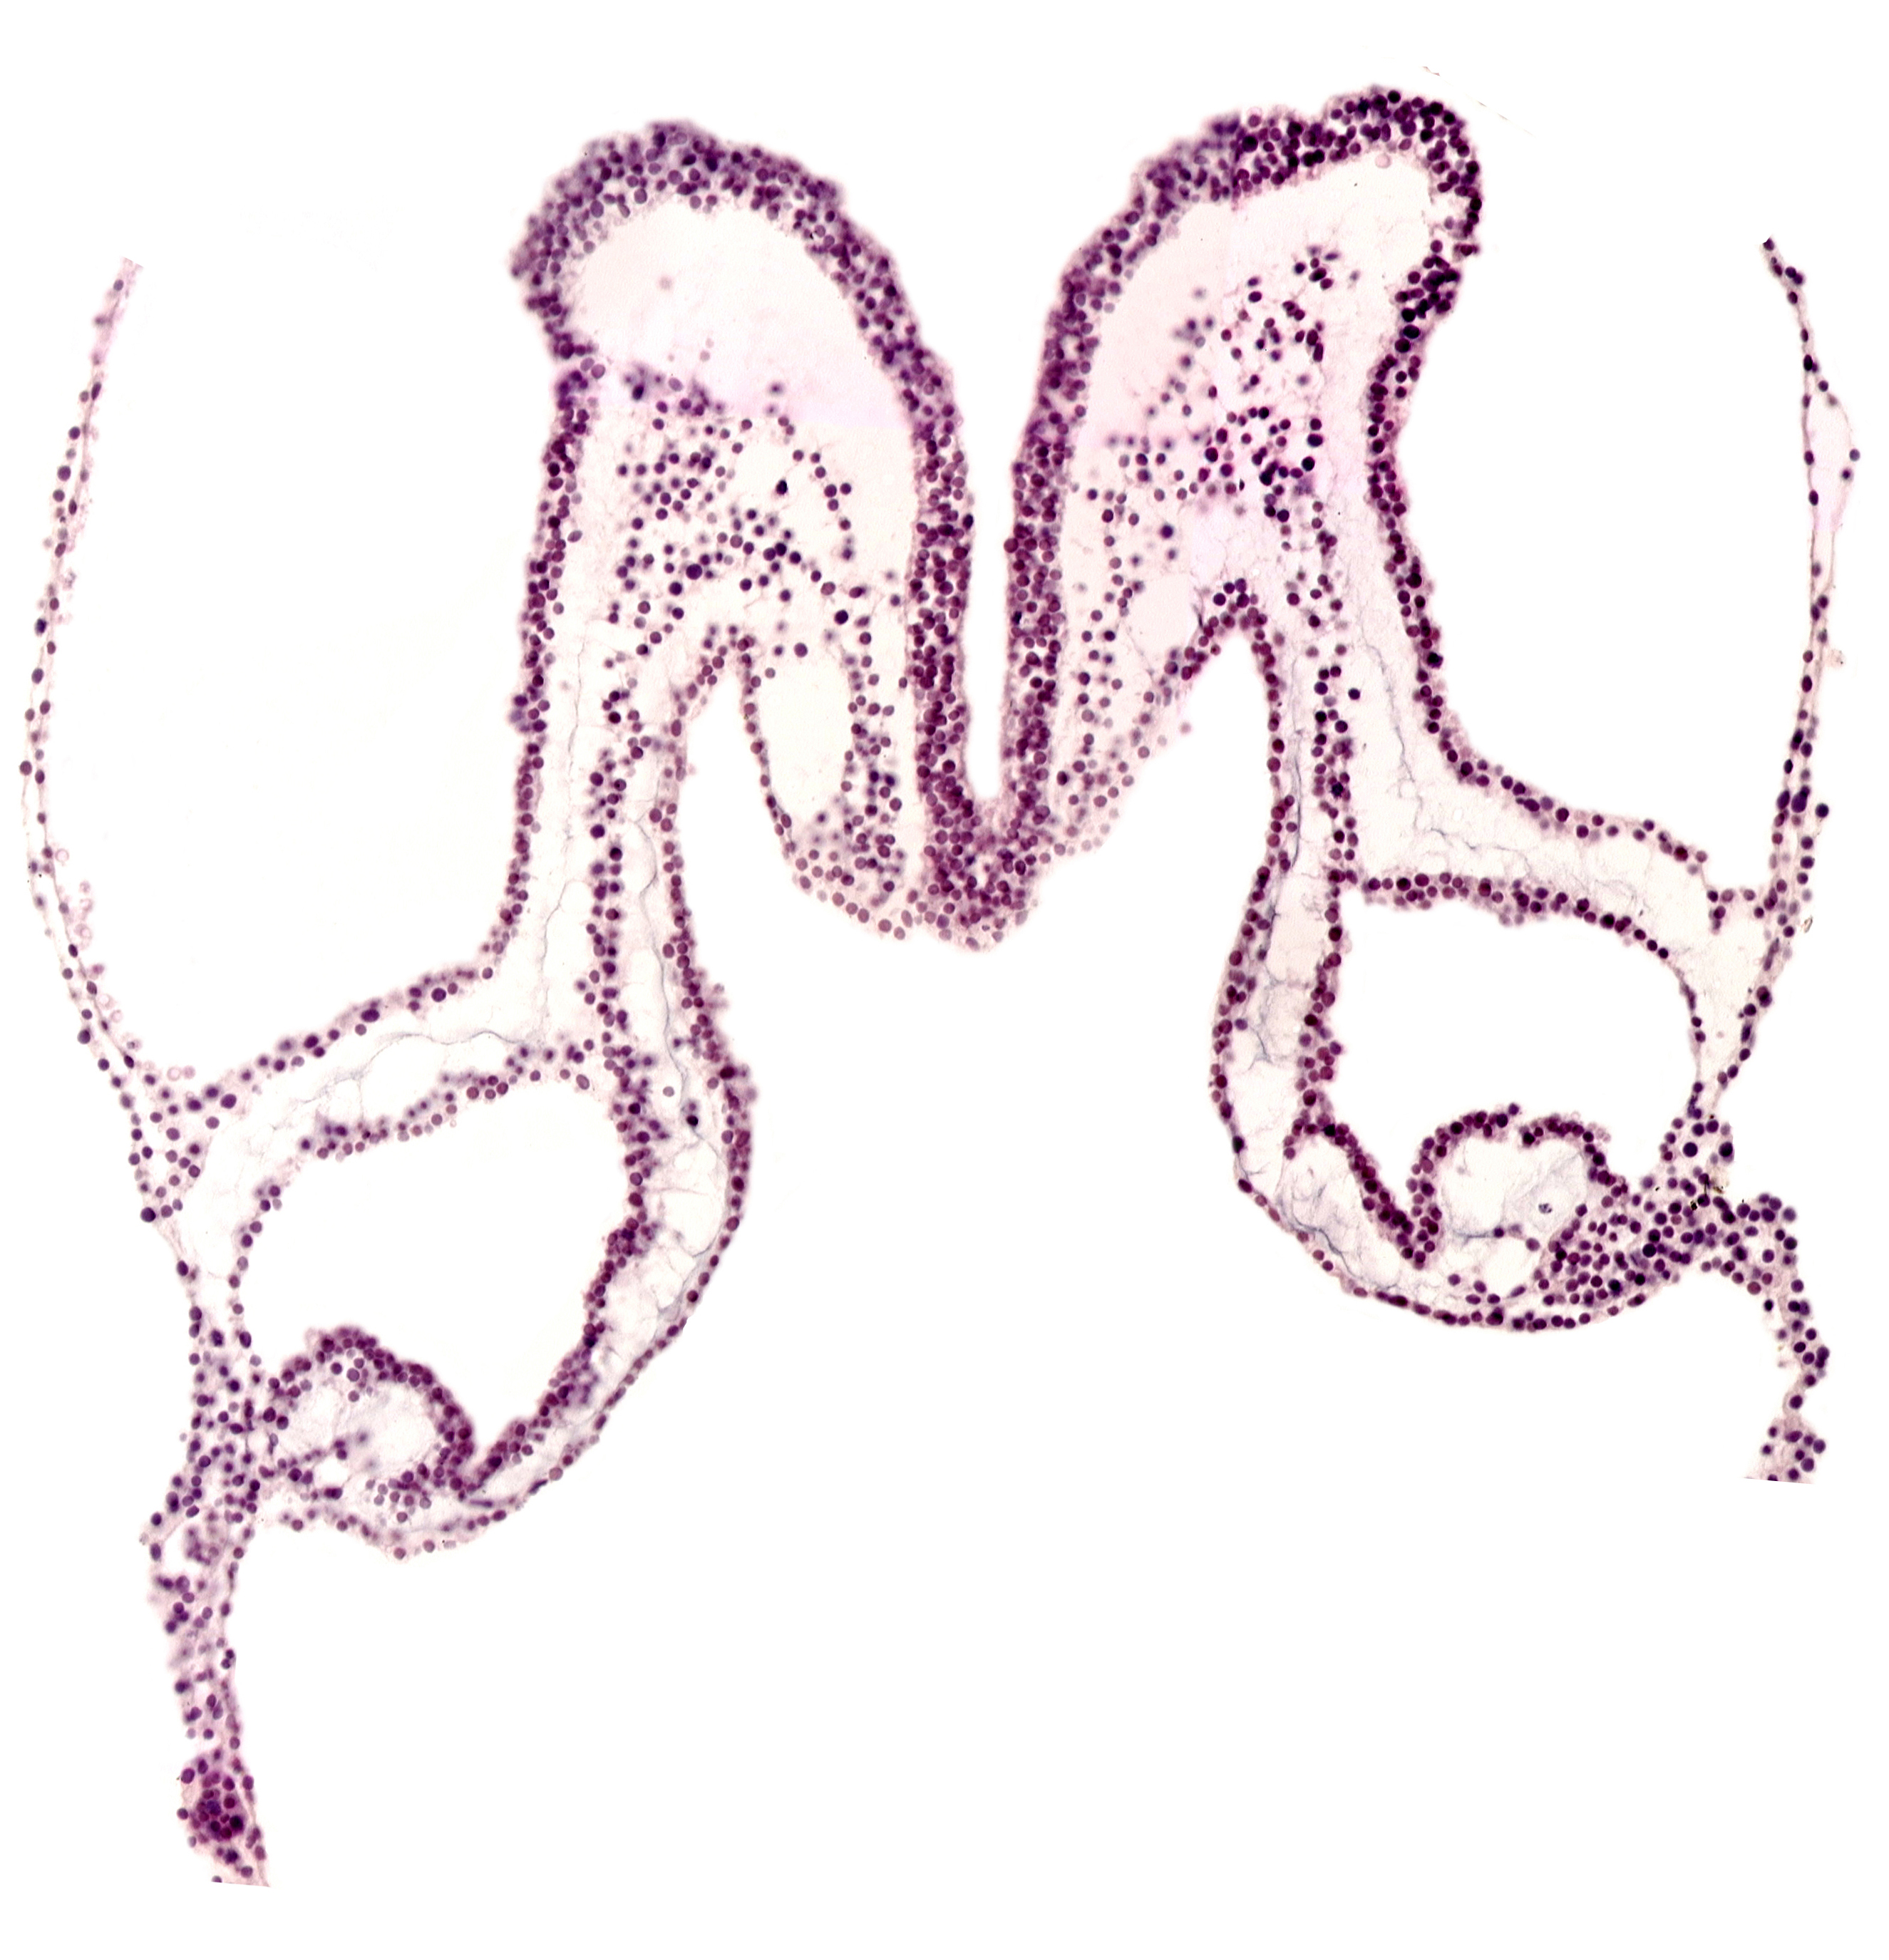

Carnegie Embryo #3709 | Location: 01-04-08

Keywords: midgut primordium (lumen), presumptive left atrium, primordial left dorsal aorta, primordial right dorsal aorta, rhombencephalon primordium (R)

Source: The Virtual Human Embryo.